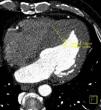

Case 1A 20-year-old man complaining of chest pain was referred for cardiac CT to exclude coronary artery anomalies. The exam showed coronaries with normal origin and course, but contrast was observed passing from the left atrium (LA) to the right atrium, raising the suspicion of a communication between the two chambers. Transesophageal echocardiography confirmed the diagnosis of ostium secundum-type atrial septal defect (Figure 1), which was closed surgically.